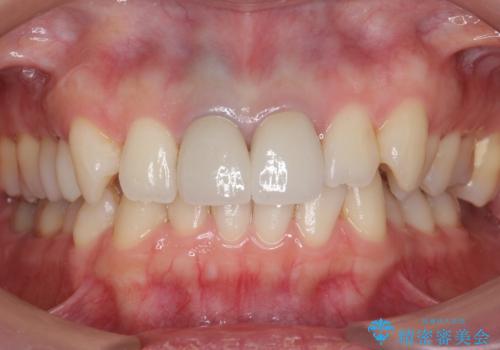

- 32万円(税別) 上顎両側1 ファイバーコア、仮歯、ジルコニアクラウン(スペシャル)費用は治療当時の料金となります

歯茎の黒ずみに関しては、中の歯の根が変色して透けている状態のため、変えることは難しいです。

笑っても歯肉が見えにくい方でしたので、問題ありませんでした。